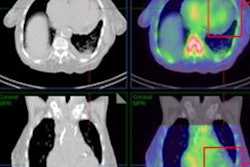

A 67-year-old man with previously diagnosed right renal cell carcinoma (RCC), post right partial nephrectomy presented with an enlarging left renal mass. Tc-99m sestamibi axial SPECT (A), and fused SPECT/CT (axial = B, coronal = C) images show a mass in the superior pole of the left kidney with its inferior part showing tracer avidity (thin arrow) and the superior part showing relative photopenia (thick arrow). It was diagnosed as a likely collision tumor on SPECT/CT with the inferior, tracer-avid region likely representing an oncocytic tumor and the superior, photopenic region likely representing a concerning RCC. Contrast-enhanced CT images (noncontrast = D, postcontrast nephrogenic phase axial = E, coronal = F) showed a solid heterogeneously enhancing left renal mass likely representing oncocytoma. The patient underwent left partial robot-assisted laparoscopic nephrectomy, and histopathology showed a collision tumor composed of clear cell RCC (rhabdoid differentiation, WHO/ISUP grade 4) and an eosinophilic variant of chromophobe RCC. Image courtesy of the Journal of Nuclear Medicine.Based on the biopsies, the researchers split the tumors into 19 "malignant/concerning" tumors (52.8%) and 17 "benign/nonconcerning" (47.2%) tumors. They then performed visual interpretations of the two imaging approaches to calculate their sensitivity and specificity for characterizing the tumors in each group.